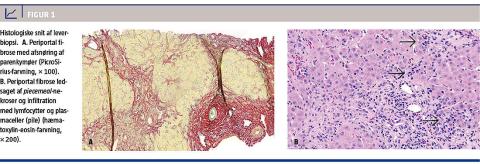

Efter to måneder var BILI-niveauet normaliseret, men pga. vedvarende parenkymatøs leverpåvirkning med et ALAT-niveau på 222 E/l blev der foretaget leverbiopsi. Denne viste kronisk hepatitis med fibrosegrad 3 og moderat inflammatorisk aktivitet, hvilket var foreneligt med AIH (Figur 1). Med baggrund i biopsisvaret blev der iværksat behandling med budesonid 9 mg × 1 dagligt, hvilket normaliserede levertallene i løbet af få uger.

AHA er en akut inflammatorisk leversygdom, der histologisk er karakteriseret af lymfoplasmacytær inflammation, periportal nekrose og centrilobulær

hepatocellulær ballooning, kolestase og nekrose.

I sjældne tilfælde ses en fulminant form af AHA med panlobulær nekrose. Ved AHA udvikles der ikke fibrose, og kroniske former kendes ikke. AIH er en kronisk inflammatorisk leversygdom, der histologisk minder om AHA. Den adskiller sig dog ved fibrose i relation til den periportale inflammation og nekrose, og ubehandlet progredierer AIH til cirrose. Patienten i sygehistorien opfyldte de internationale kriterier for diagnosen AIH (autoimmun prædisposition, typisk biokemi, autoimmun serologi og karakteristisk histologisk billede) [2]. Amlodipininduceret medikamentel hepatitis blev udelukket pga. den stabile behandling igennem en årrække.